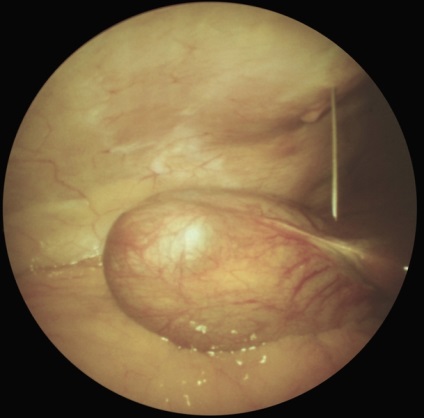

Laparoszkópia nőgyógyászat diagnosztikai és terápiás lehet előállítani bevezetésével laparoszkóp a hasfalon keresztül, vagy egy bemetszésen keresztül a posterior vaginális boltozatot (culdoscopy). Javallatok sürgősségi tartja az AL a nőgyógyászati gyakorlatban is gyanús petevezeték terhesség. piosalninks, apoplexia vagy petefészek ciszta, méh perforáció, és így tovább. d. A rutinszerűen elvégzett L. (culdoscopy) hosszan tartó kismedencei fájdalom ismeretlen etiológiájú, algomenoree súlyos, nehezen gyógyítható a szokásos orvosi terápiás módszerek gyanúja belső nemi rendellenességek és más szervekben. Contra L. hajtjuk a hasfalon keresztül ugyanazok, mint az L. vállalta, hogy vizsgálatát a hasüregbe. Culdoscopy ellenjavallt a súlyos összenövések pozadimatochnom térben a tumorokat a medence. Laparoszkópos kép savós petefészek ciszta ábrán látható. 4, valamint. Laparoszkópia is végezni néhány terápiás tevékenység: koaguláció és boncolása összenövések (. 4. ábra, b, c), endokoagulyatsiyu heterotopical gócok endometriumbiopszia petefészek punkció retenciós ciszták és mások.

Ábra. 4a). Laparoszkópos képet néhány nőgyógyászati betegségek - savós petefészek ciszta.